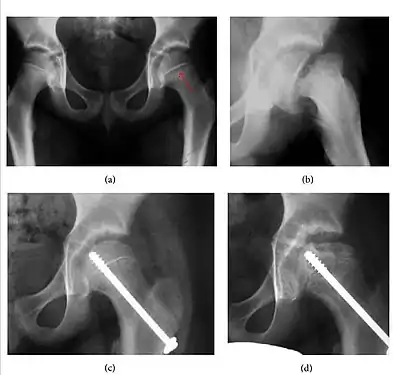

Plain radiography allows us to categorize the hip as normal or dysplastic or with impingement signs (pincer, cam, or a combination of both). Besides these, pathologic processes like osteoarthritis, inflammatory diseases, infection, or tumors can also be identified (Figure 1).[1]

Figure 1.

Slipped capital femoral epiphyses (SCFE) usually affect 11- to 14-year-old adolescents (Figure 4). Radiographs may show widening and irregularity of the physis and posterior inferior displacement of the capital femoral epiphysis. On the AP view Klein’s line, tangent to the lateral aspect of the femoral neck, does not intersect the femoral head indicating that it is displaced. SCFE may compromise the blood supply to the femoral head and cause avascular necrosis, mainly when there is instability between the fragments.[1]

Figure 4: (a) X-ray of a 10-year-old child with left hip pain. It was considered normal at emergency despite the widening of the left physis (arrow). Two weeks later epiphysiolysis was evident (b). Despite appropriate surgical reduction (c) osteonecrosis developed and femoral head collapsed 1 month later (d).[1]